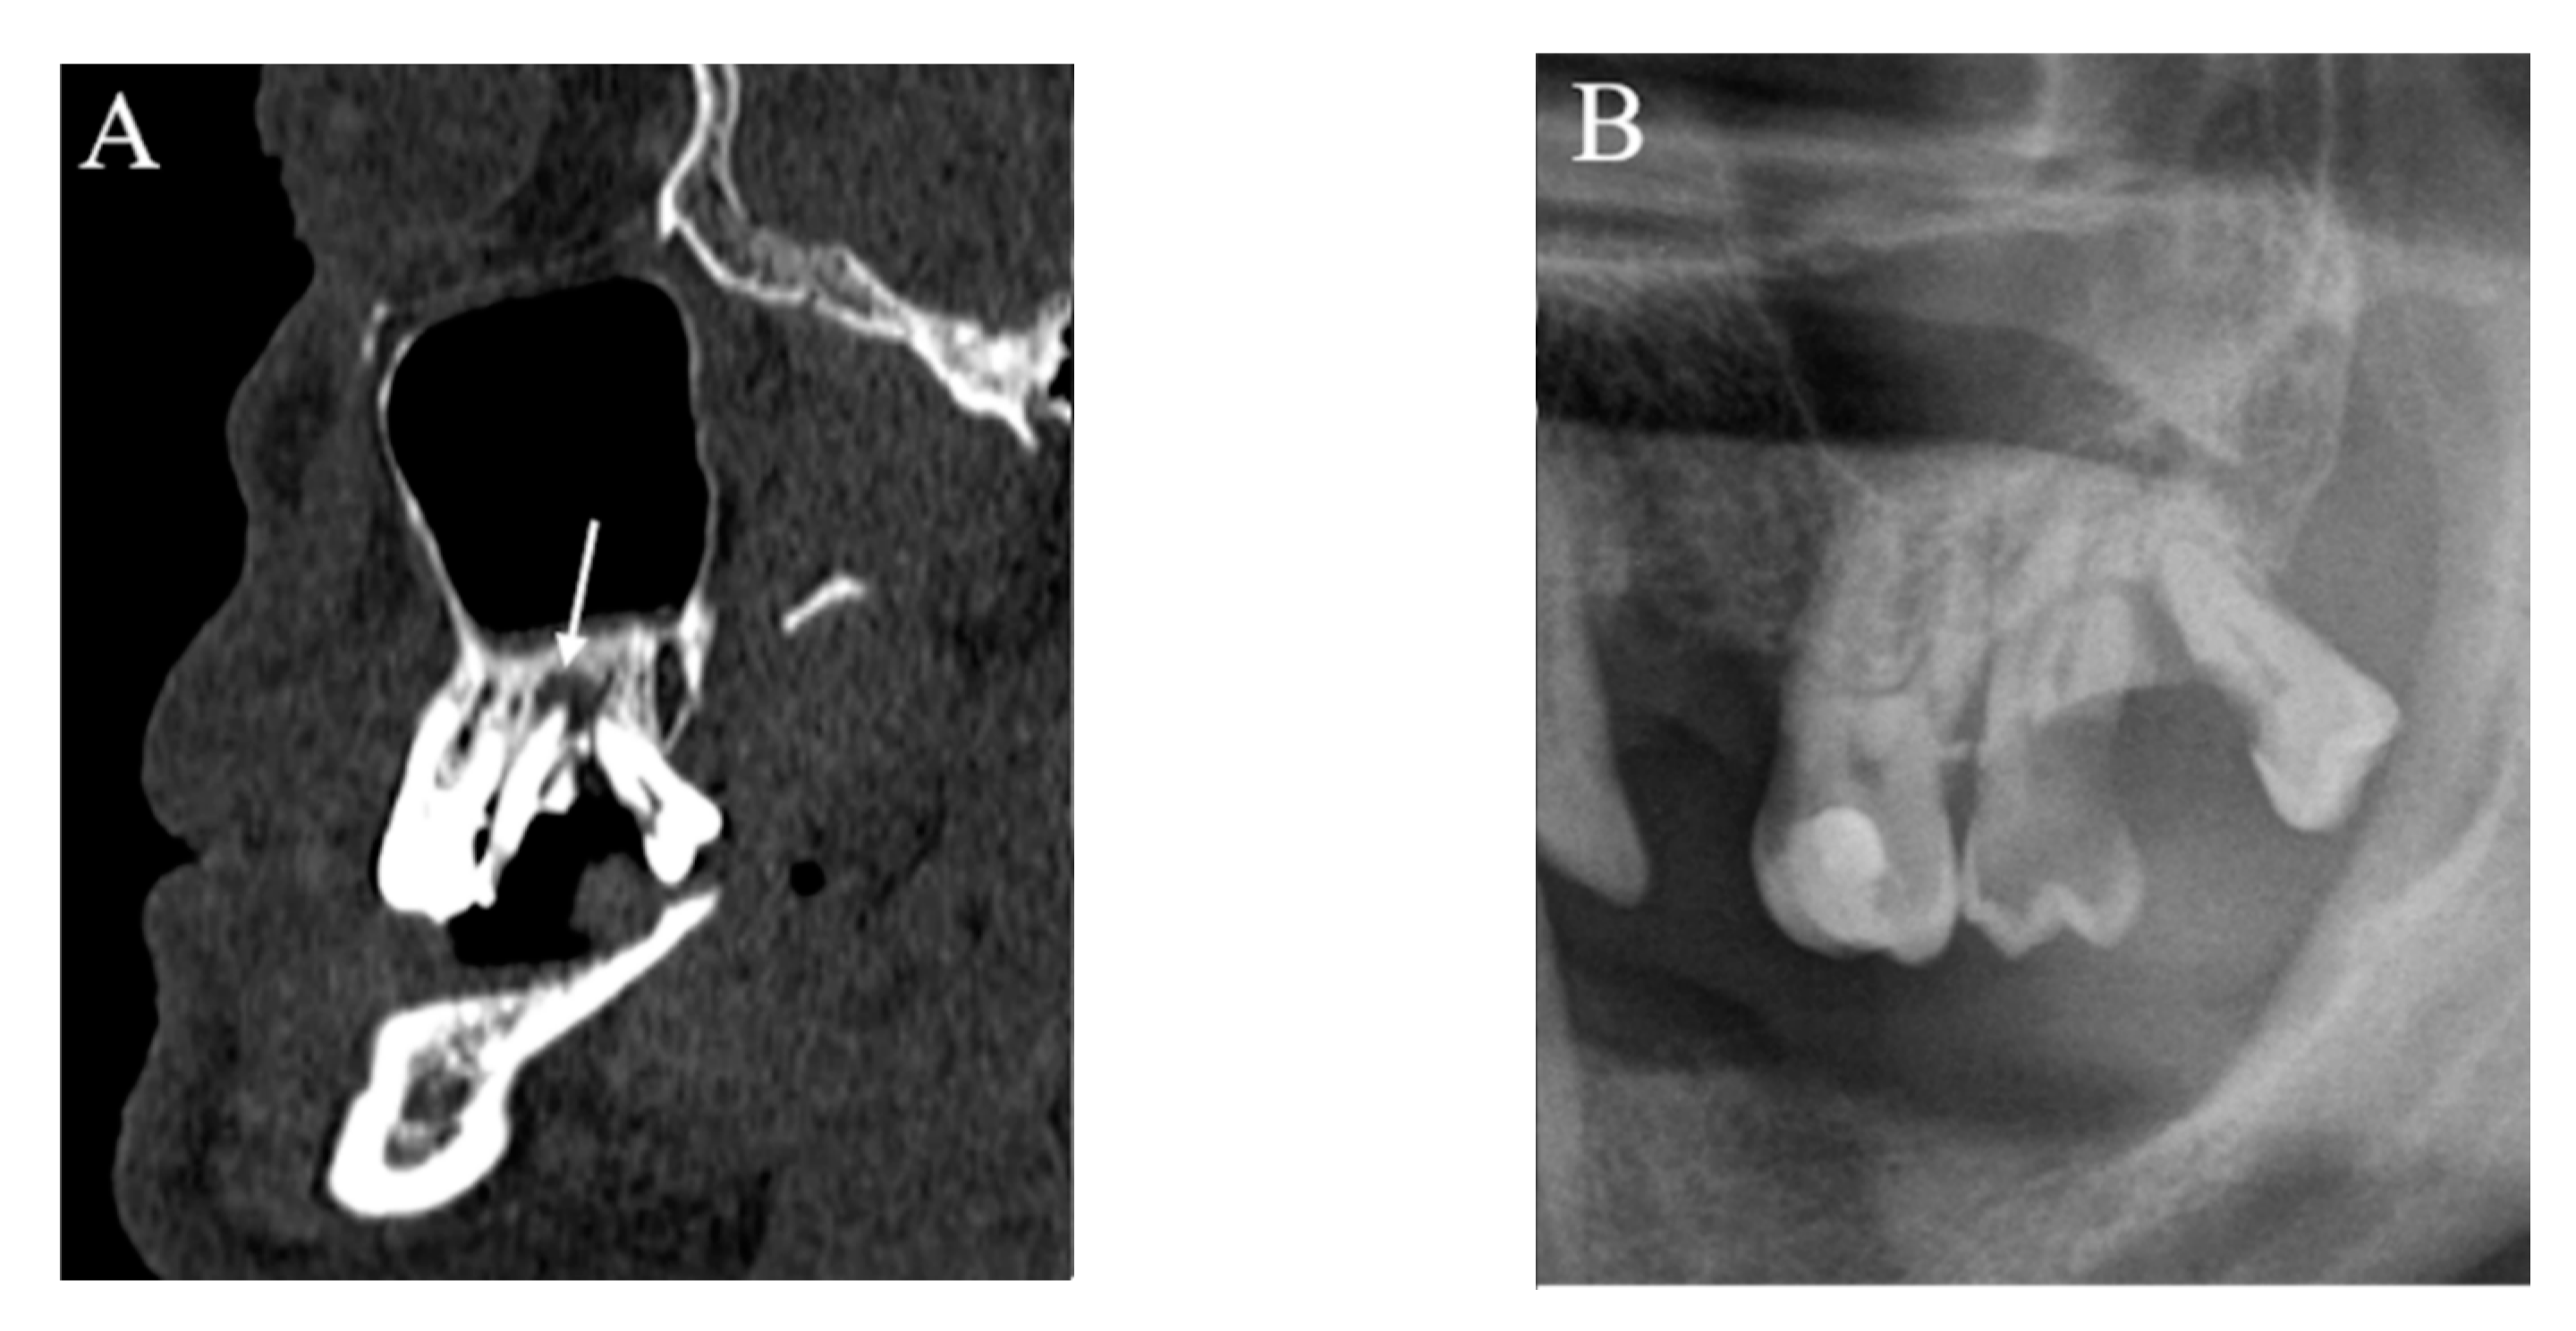

No false positive or false negative was found in the assessment of deep caries, root remnants, and stage III periodontal disease, whereas false positives were very few (2.6%) (Figure 2) and false negatives accounted for just over half of the cases (53.2%) for AP lesions (Figure 3).

Figure 3.

An example of false-negative apical periodontitis. (B) Upper jaw MSCT imaging showing apical periodontitis affecting the left second molar. (A) In PAN, no periapical bone lesion was detected at the level of the periapex of the left second molar.